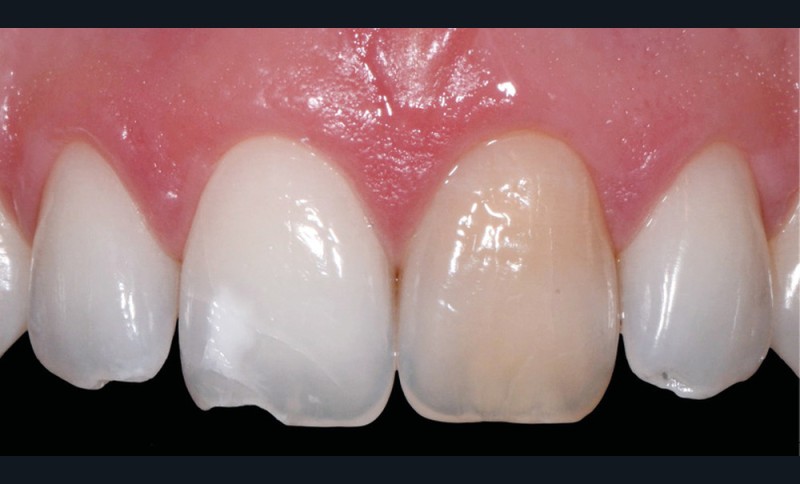

Elles intéressent la structure organo-minérale de la dent par incorporation de molécules colorées au sein du complexe amélo-dentinaire. Elles peuvent être liées à la prise de médicaments (fig. 2a), à des maladies génétiques ou congénitales. Elles peuvent également être la conséquence d’une pathologie pulpaire (fig. 2b) ou d’un acte technique (fig. 2c, d) [2, 4].